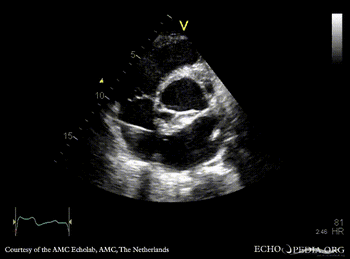

Abscess of aortic valve prosthesis

Courtesy of: AMC Echolab, AMC, The Netherlands

E00844.gif E00845.gif

PLAX: abscess of aortic valve prosthesis PLAX with Color Doppler: severe mitral regurgitation